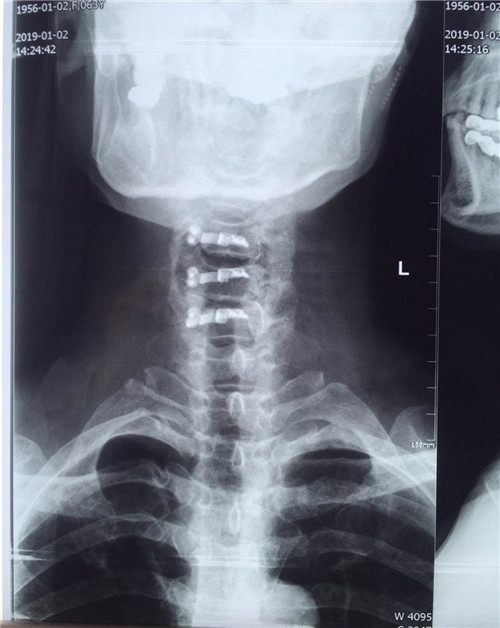

术后

患者入院后,骨一科医护人员为其做进一步检查,诊断为多发颈椎间盘突出并继发颈椎管狭窄症。经讨论研究后,程福宏副主任医师决定为其行颈后路颈4、5、6的单开门椎板扩大成形术,该手术在王小峰主治医师的配合下完成。术中,医生为患者进行彻底的减压脊髓,固定椎板。术后患者恢复较好,症状改善明显,已能够独自行走,恢复正常活动。